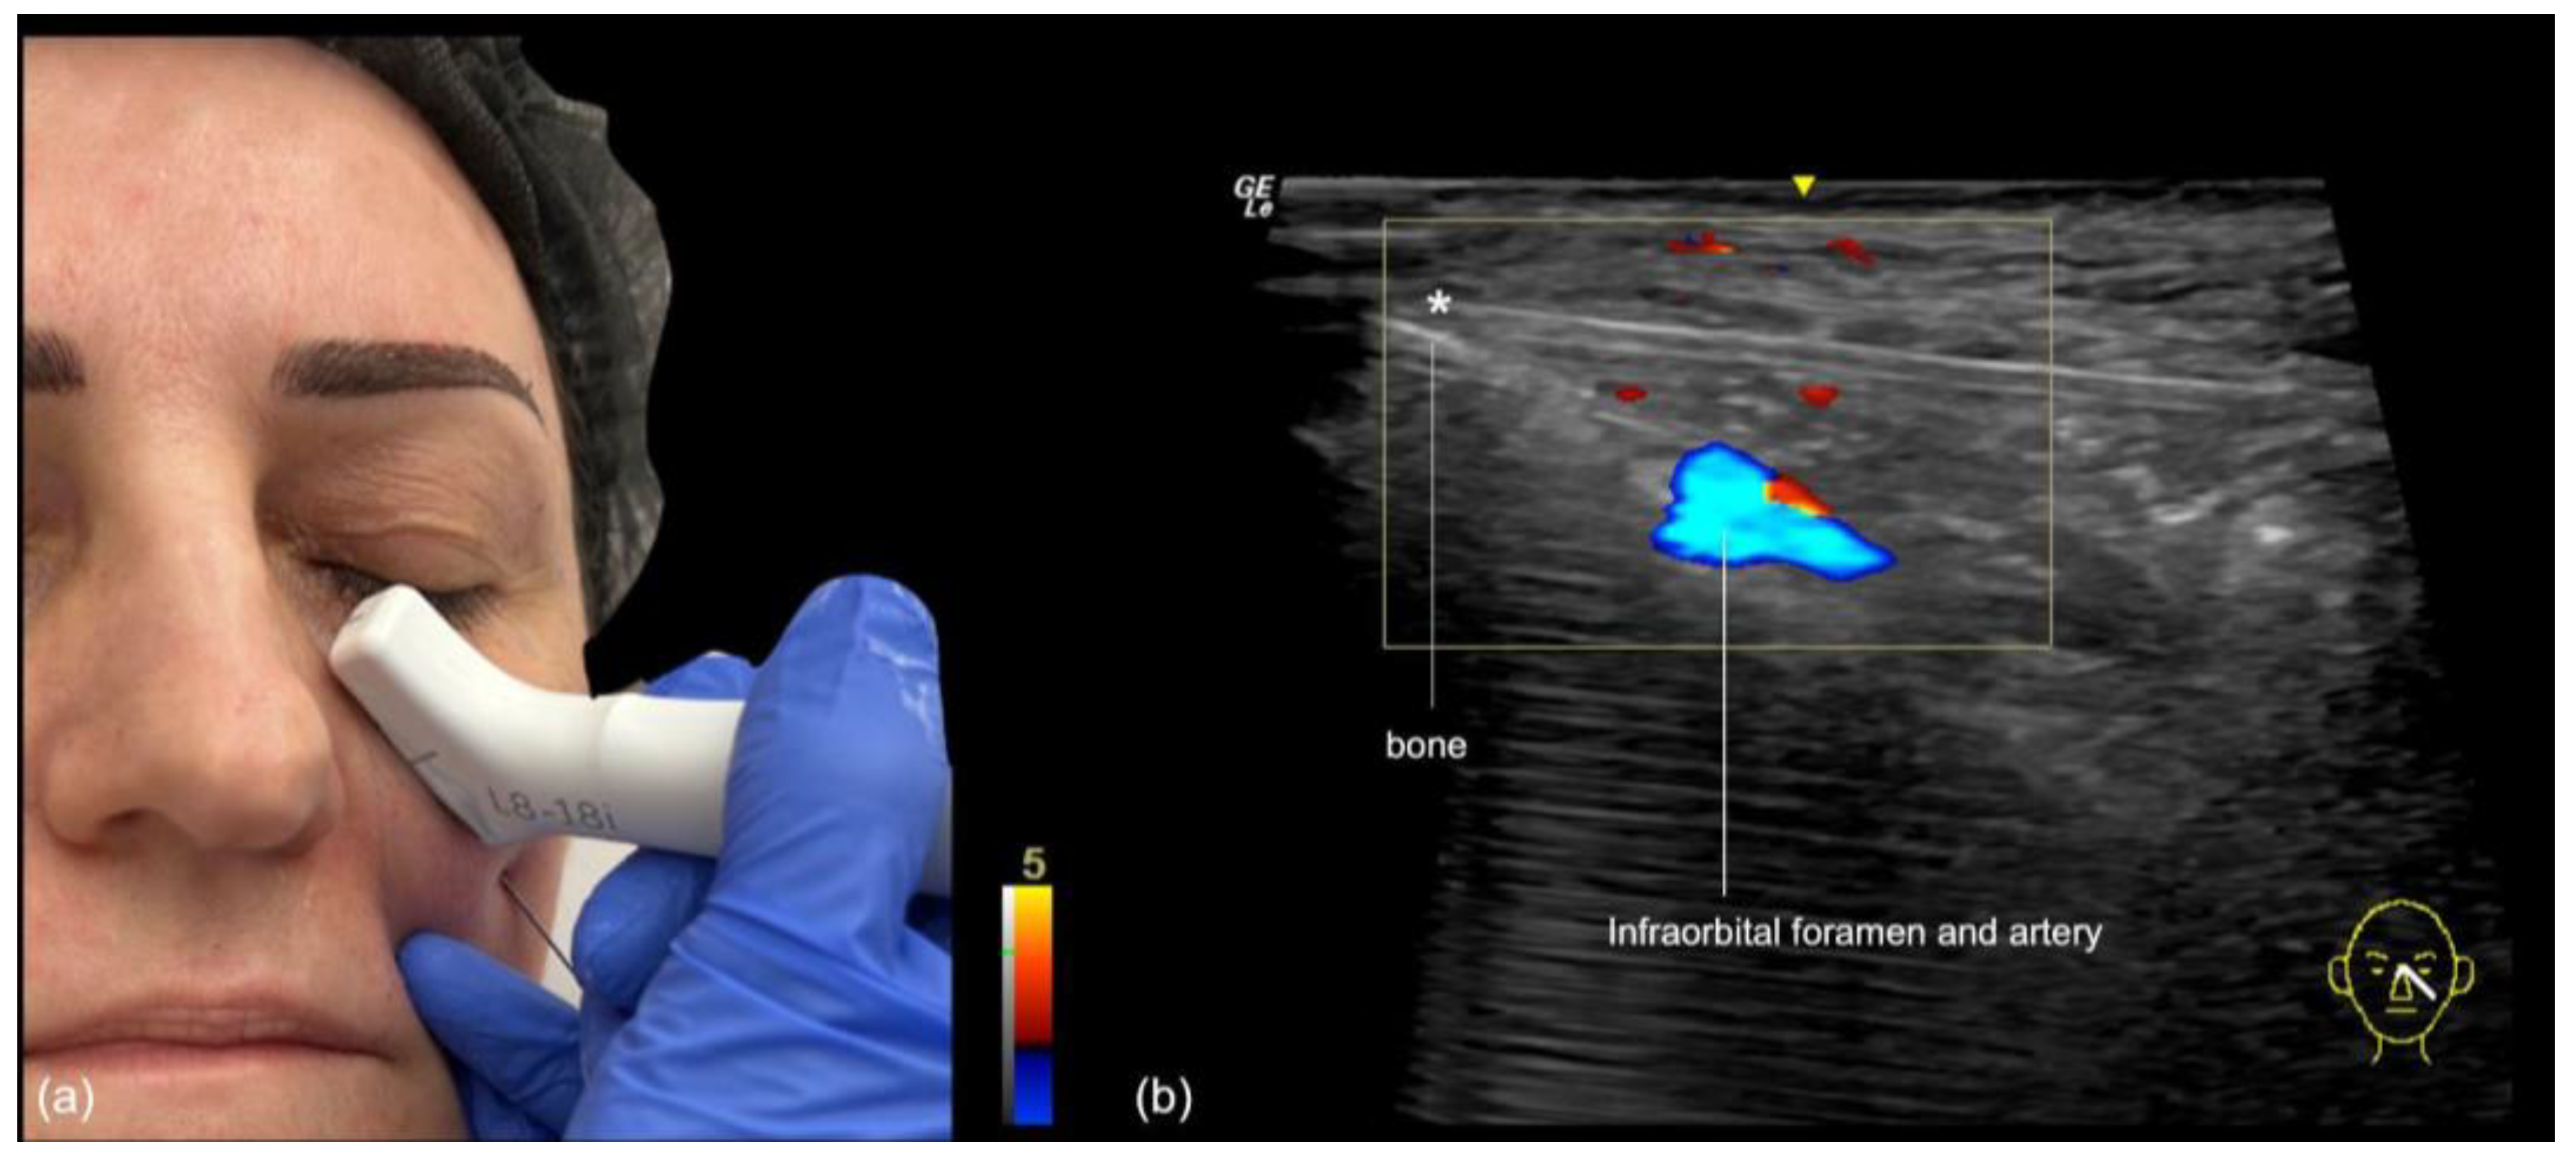

- Blunt cannula injection: To volumize the region, our preferred approach is the use of a cannula, which is kept in the deep subcutaneous plane. While the risk of occlusion is lower, there is still the possibility of compressing the infraorbital foramen with the filler, often resulting in persistent pain or paresthesia. A good strategy is to use ultrasound to identify the foramen in advance (Figure 8), mark it on the skin, and avoid this area during the cannula injection. The “scan while injecting” technique can also be used when the cannula is very close to the marked location of the foramen on the skin, to ensure that no injection occurs near it.